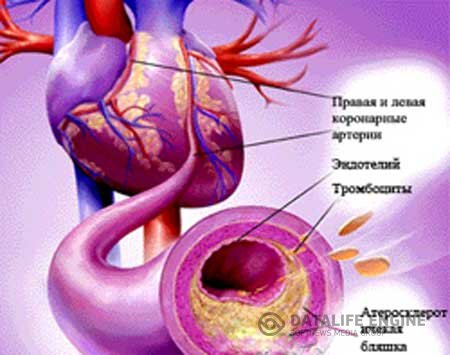

АтеросклерозАтеросклероз является одним из самых частых заболеваний современного человечества. Он поражает в основном... АтеросклерозАтеросклероз является одним из самых частых заболеваний современного человечества. Он поражает в основном...